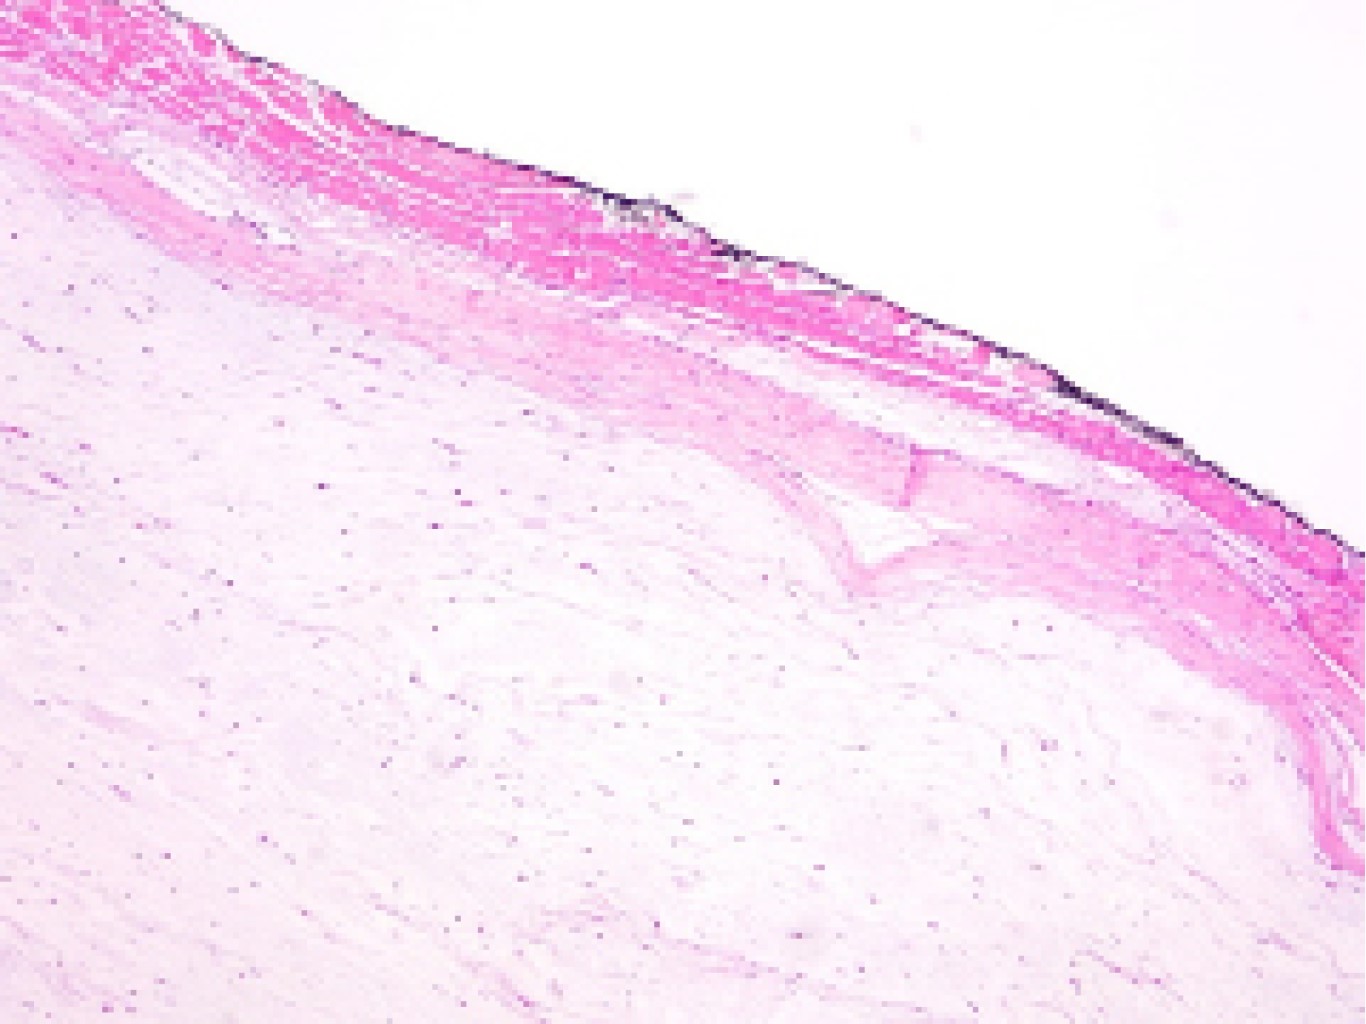

El reporte histopatológico mostró una masa uniforme, al corte muestra superficie blanquecina transparente de aspecto mixoide y de consistencia gelatinosa (Figura 5). En múltiples cortes teñidos con hematoxilina-eosina se reconoce neoplasia hipocelular, hipovascular, de aspecto homogéneo con abundante matriz mixoide. No se registra actividad mitósica ni necrosis tumoral. Se observa quistificación focal (Figura 6).

Figura 5

Figura 6